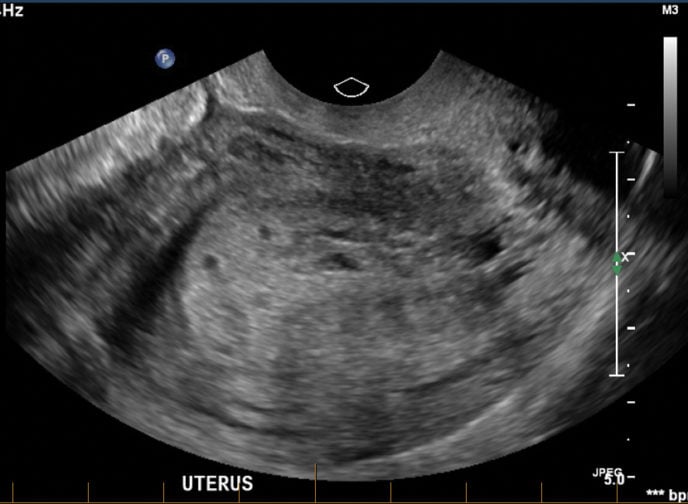

Molar Pregnancy - WikEM

pregnancy molar ultrasound wikem transvaginal